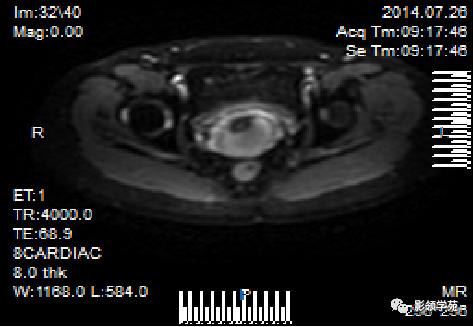

宫颈癌MRI表现

宫颈癌可表现为类圆形或不规则形肿块,在T2WI上表现为均匀或欠均匀的高信号,与正常宫颈基质及宫旁脂肪形成良好的自然对比。

- Ⅰ期肿瘤:侵犯宫颈基质,T2WI等信号肿块,宫颈管扩大及宫颈纤维基质中断

- Ⅱ期肿瘤:宫颈增大,宫旁肿块或宫旁脂肪组织内出现异常信号的粗线状影

- Ⅲ期肿瘤:侵犯至阴道下部,外延至盆壁,或出现肾积水。

- Ⅳ期肿瘤:膀胱壁或直肠壁低信号中断,膀胱壁或直肠壁增厚或腔内肿块。